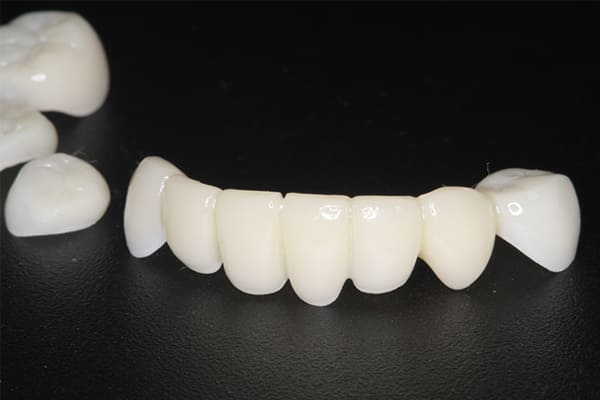

精密な型どり

完成前に適合や見た目のチェック

精密な型どりは、通常保険治療では使用しない、この患者様だけに合った型を取るトレーを作製、また寸法変化の最も少ない精密なシリコンを用いてお口の中を精密に限りなく再現する型どりの方法で型をお取りしました。

完成前に適合や見た目のチェックでは、咬む力で義歯がたわみ、残りの歯に負担がかからないよう、見えない内側は、金属を用い、強度を増し、また金属のため薄くすることで違和感をなくす設計とし、完成前に試し合わせを行い、装着感、審美性を確認しました。